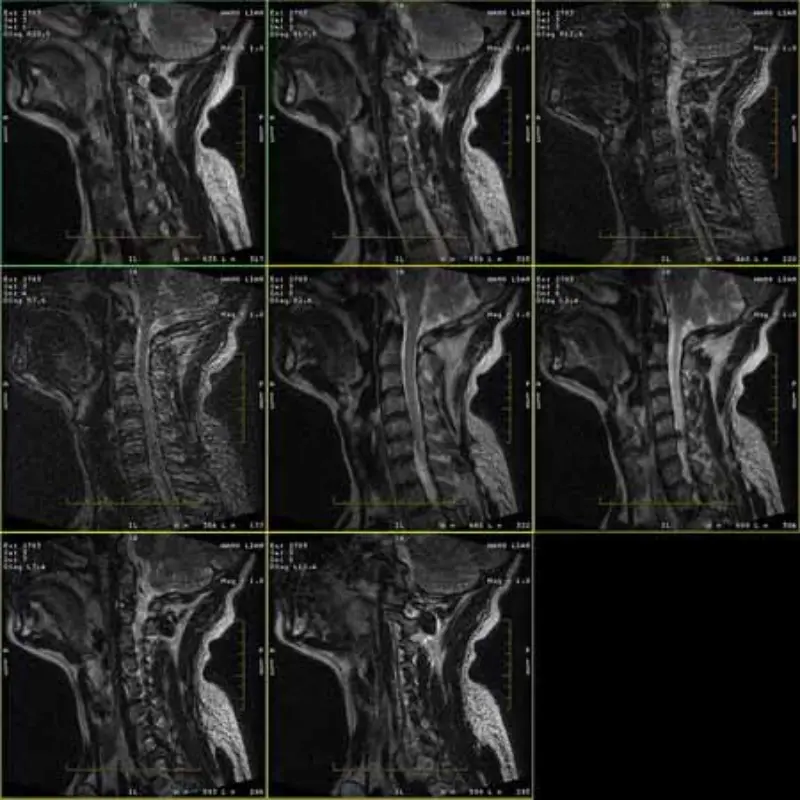

تحتوي صور بروتوكولات FRFSE وGRE على صور شبحية وأحيانًا تظهر صور منخفضة SNR في سلسلة واحدة. لكن صور بروتوكول SE طبيعية.

1. هذه المصنوعات تحدث فقط في صورة بروتوكولات FRFSE وGRE، ولكن بروتوكول SE

الصور لا تظهر أبدا . قم بإجراء فحص سريع لـ Head SPT، حيث أن نسبة SNR للرأس هامشية (حوالي 8.2).